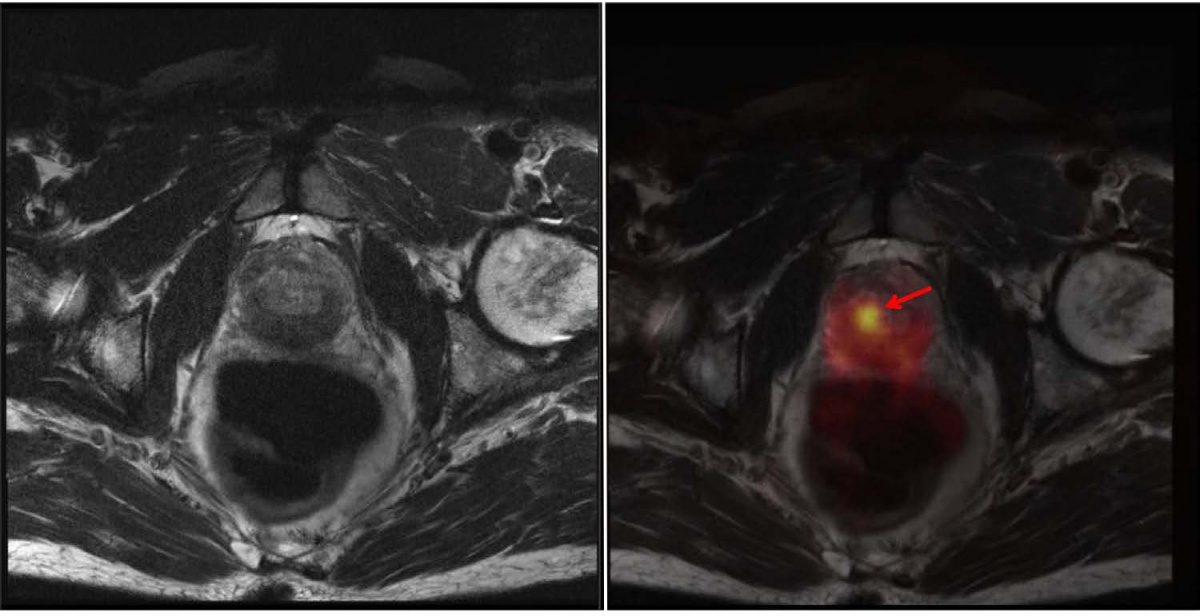

In einem zweiten Fall konnte ein kleiner, 9 x 8 mm messender Lymphknoten links infrapubisch mit deutlich gesteigerter PSMA–Avidität im PET/CT aufgrund des sogenannten „Halo-Artefaktes“ im PET/MRT nicht verifiziert werden. Der Lymphknoten wies einen erhöhten standardized uptake value (SUV) im PET/CT von 10,1 auf und war somit als eindeutig malignomsuspekt zu werten (Abbildung 4). Im MRT kam der Lymphknoten morphologisch als T2-hyperintens zur Darstellung, zeigte jedoch aufgrund eines ausgedehnten Halo-Effektes keine gesteigerte PSMA–Avidität im PET/MRT (Abbildung 5). In der Literatur wird der „Halo-Artefakt“ als typische Artefaktbildung im PET/MRT, die die Detektion von malignen Läsionen nahe der Harnblase bzw. der Nieren beeinträchtigt, beschrieben [3, 21].

MRT (links, Sequenz: STIR transversal) ohne Nachweis einer gesteigerten PSMA-Avidität im PET (rechts)